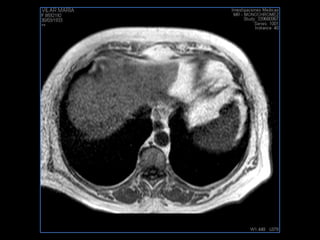

PROTOCOLO hígado graso AXIAL in phase y out phase AX T1 y AX fat sat +SAG T2  CON   GADOLINIO :  COR T1+AX T1(DIN) SAT: NO  FASE: RL THK: 4MM  COIL:  GAP: (FACTOR 1.4)  FOV: 40 CM NEX:2 SINCRONIZACION RESPIRATORIA EN 3 O 4 CICLOS ALE

PROTOCOLO hemocromatosis AXIAL supresión grasa /AX multieco en higado COR T2 AX T1 +SAG T2  CON   GADOLINIO :  COR T1+AX T1 SAT: NO  FASE: RL THK: 4MM  COIL:  GAP: (FACTOR 1.4) 1MM FOV: 40 CM NEX:2 SINCRONIZACION RESPIRATORIA EN 3 O 4 CICLOS ALE